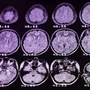

Landet Fisch häufig am Teller, kann das den Verlauf der Multiplen Sklerose verlangsamen

Isst man mehr Fisch, so kann dies das Fortschreiten einer MS-Erkrankung verlangsamen. Der Effekt scheint aber nicht von den Omega-3-Fettsäuren ausgelöst zu werden.

• Häufiger Fischkonsum kann das Fortschreiten der Multiplen Sklerose (MS) verlangsamen, unabhängig von Omega-3-Fettsäuren.

• Eine schwedische Langzeitstudie zeigt, dass Fischkonsum das Risiko einer Verschlechterung der Behinderung bei MS-Patienten reduziert.

• Der höchste Fischkonsum bei Diagnose war mit einem um 44% geringeren Risiko einer Behinderungsverschlechterung verbunden.

• Fischkonsum wirkt unabhängig von anderen Lebensstilfaktoren wie körperlicher Aktivität oder Gewicht.

• Die Aminosäure Taurin im Fisch könnte eine schützende Wirkung gegen MS haben.